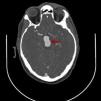

Medicina Clínica Aneurisma gigante de la arteria basilar en un varón joven

Aneurisma gigante de la arteria basilar en un varón joven

A giant basilar-artery aneurysm in a young male